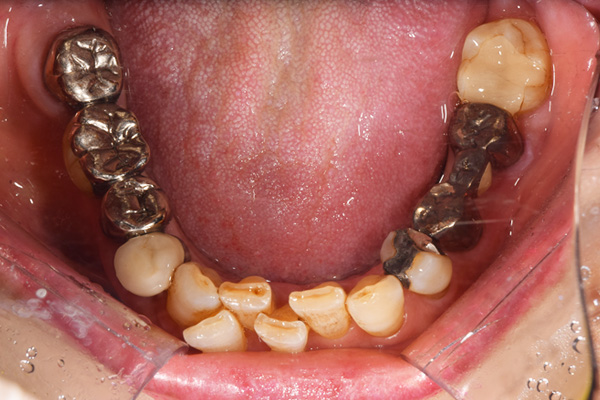

上下の入れ歯が外れやすくなったということでいらっしゃいました。 顎の骨はしっかりしていましたので、精密な型取りさえすればしっかりした入れ歯がつくれると思いました。 また下には6本歯が残っていましたが、虫歯になっている歯もありました。 かぶせ物のなかで大きな虫歯があった歯があり、1本だけ残せない状態でした。

上の入れ歯は確かに吸着は甘くなっていました。 また下の入れ歯はバネの一部が壊れており、安定感がなくなっていました。